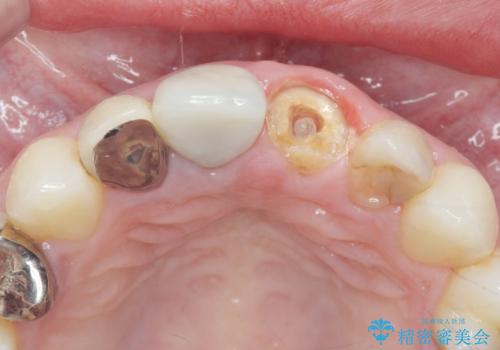

- 過去に他院で治療した前歯が取れたとの事で来院。

被せ物だけでなく中の土台まで取れていました。

歯の根っこのお掃除(根管治療(保険))を行い、土台を立ててセラミックの被せ物で治療しました。

また、隣の歯も被せ物の適合が悪く予後がよくないので根管治療(保険)を行い、セラミックの被せ物で治療を行いました。